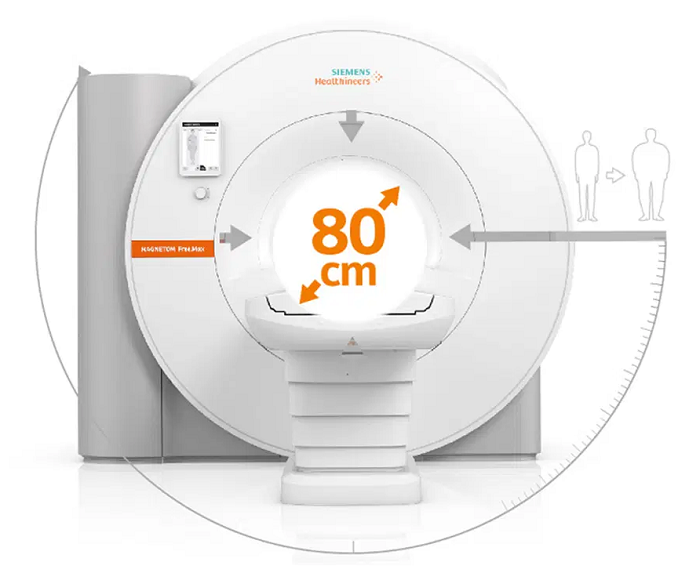

- Where patients have felt discomfort, MAGNETOM Free.Max is the world’s first 80 cm bore offering an improved patient experience

Expand opportunities with a larger bore

Bore size should not prevent patients from having an MRI. However, whether it is due to claustrophobia or a larger body, sometimes it does happen. For a more comfortable and less daunting experience, a larger bore size would help. Opening up the bore means that there is better access and new opportunities.

The first 80 cm patient bore

The first step of patient care is putting the patient at ease. Using the first and only 80 cm patient bore, MAGNETOM Free.Max overcomes limitations associated with accessibility and patient comfort, thereby making the experience a realistic choice for anxious, claustrophobic, and more corpulent patients.

The first 80 cm wide bore redefines patient accessibility

The 80 cm wide bore of MAGNETOM Free.Max in comparison to conventional bore sizes. Image Credit: Siemens Healthineers

The extra wide bore provides greatly improved access for bariatric patients. Image Credit: Siemens Healthineers

The 80 cm patient bore strongly reduces anxiety and increases patient comfort. Image Credit: Siemens Healthineers

Extra wide bore with 80 cm. Image Credit: Siemens Healthineers